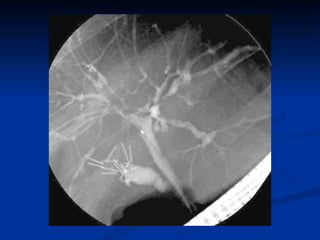

Dignosis/assessing severity of extent: Imaging Abd XRs are helpful in diagnosing bowel obstruction / dilatation in patients with CD & UC. Radiographs of small bowel are more useful for evaluating CD.  Barium radiographs, enteroclysis, CT enterography, capsule endoscopy are also helpful.  Although no single test is ideal, CT enterography is being used more often because this study can assess various signs of inflammation & detect extraluminal findings such as fistulas & abscesses.  Capsule endoscopy is a sensitive test for identifying small bowel ulcers but should not be used in patients with obstructive symptoms because the capsule can be retained in the intestine.

Dignosis/assessing severity ofextent: Imaging Abd XRs are helpful in diagnosing bowel obstruction / dilatation in patients with CD & UC. Radiographs of small bowel are more useful for evaluating CD. Barium radiographs, enteroclysis, CT enterography, capsule endoscopy are also helpful. Although no single test is ideal, CT enterography is being used more often because this study can assess various signs of inflammation & detect extraluminal findings such as fistulas & abscesses. Capsule endoscopy is a sensitive test for identifying small bowel ulcers but should not be used in patients with obstructive symptoms because the capsule can be retained in the intestine.